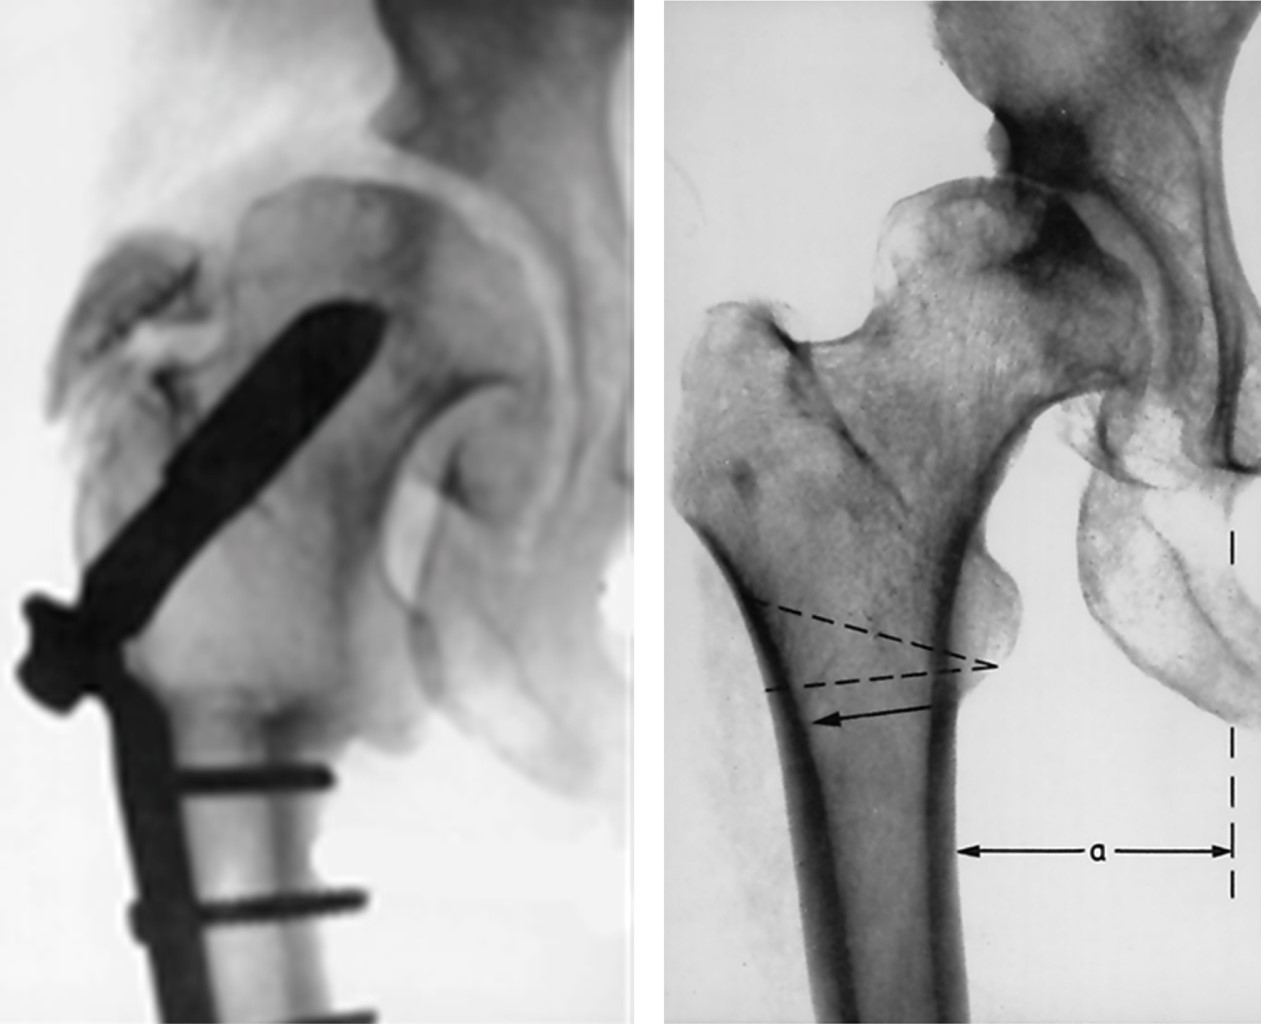

Otro hito en el desarrollo de la artroplastía endoprotésica de la cadera ocurrió en 1938 cuando Phillip Willes40 implantó en Londres la primera artroplastía total de cadera no cementada utilizando componentes de acero inoxidable (Figura 10). Antes de este hecho es importante dar crédito a Gluck,33 quien tiempo atrás (1890) implantó por primera vez cuerpos extraños en forma de prótesis total fabricados con una cabeza y una cuenca de marfil. Estos implantes se fijaban con un material plástico que él ideó (aún no existía el cemento para hueso).

Regresando a la prótesis de Willes, la estabilidad se aseguraba a través de una placa atornillada extramedularmente en superficie lateral de la diáfisis femoral. El acetábulo se estabilizaba mediante una extensión con tres bucles donde se fijaba con tornillos (Figura 3). Insistimos en recordar que aún no aparecía el cemento para hueso. La prótesis de Willes ha servido de inspiración para otros implantes similares como la prótesis Thrust-Plate® que fue diseñada por Huggler y Jacob en 1978 (Figura 11). Aunque ya no se fabrica, sus resultados a largo plazo (de 15 a 20 años) han sido satisfactorios según un informe publicado en 2016.41

El siguiente hito ocurrió en 1943, cuando Moore y Bohlman,42 trabajando en Austenal Labs (que se convertiría más tarde en Howmedica), diseñan una prótesis que invade el espacio intramedular metadiafisiario con vástagos formales (no sólo con "espigas"), con el fin de mejorar la estabilidad del implante. Hasta antes de esta propuesta, ninguna prótesis invadía el espacio intramedular con el concepto de estos autores. La prótesis de Moore (Figura 12A) fue modificada por el mismo autor y el diseño final cuenta con perforaciones a nivel de su tercio proximal para facilitar la fijación por crecimiento óseo por invasión en esos sitios.43 Casi al mismo tiempo Fred Thompson44 e Irwing S. Leinbach45 presentan otros modelos de hemiprótesis no cementada con invasión endóstica del fémur (Figura 12B y C).